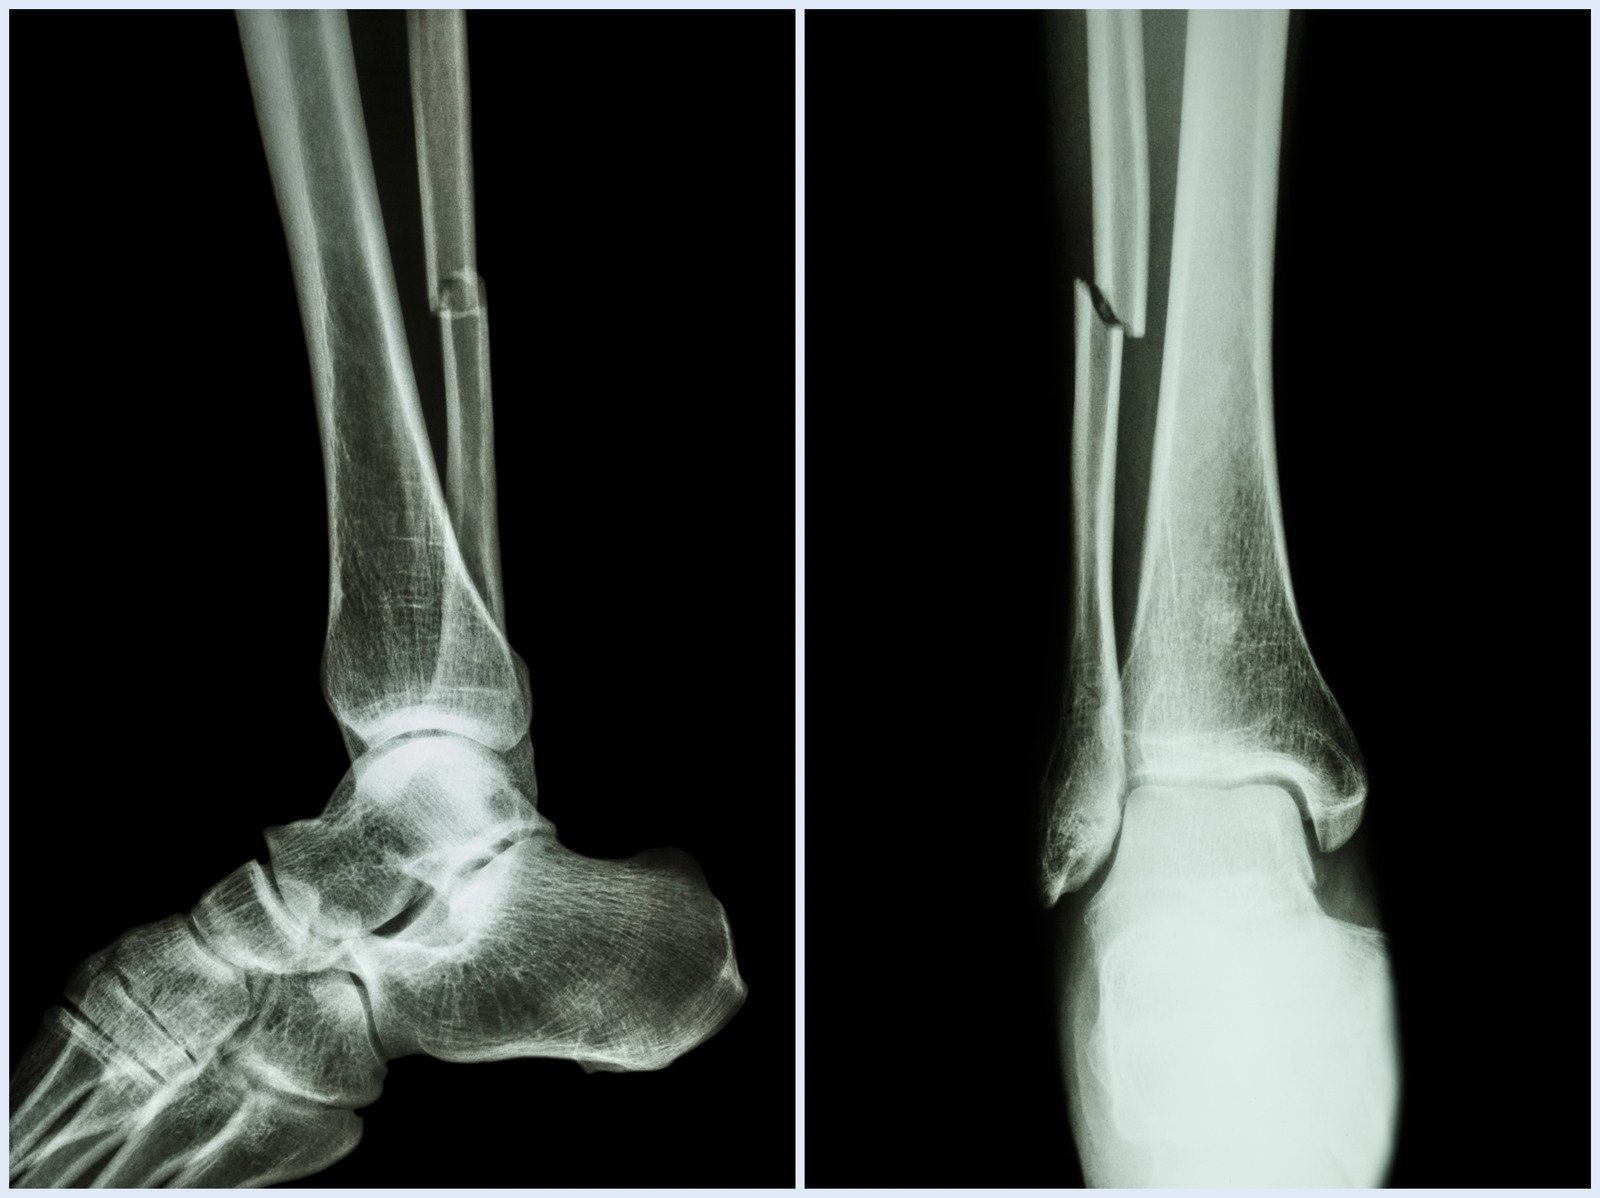

발목 골절은 교통사고, 높은 곳에서의 추락, 직접적인 충격 또는 스포츠 활동 중에 발생할 수 있습니다.

특히 발목이 비틀리거나 불안정한 표면에서의 부적절한 착지로 인해 발생하기도 합니다.

골절의 심각성에 따라 수술이 필요할 수 있으며, 골절이 불안정하거나 관절 내에 위치하는 경우, 적절한 정렬과 고정을 통해 발목의 기능을 회복하고 장기적인 문제를 예방하기 위해 수술적 개입이 고려됩니다.